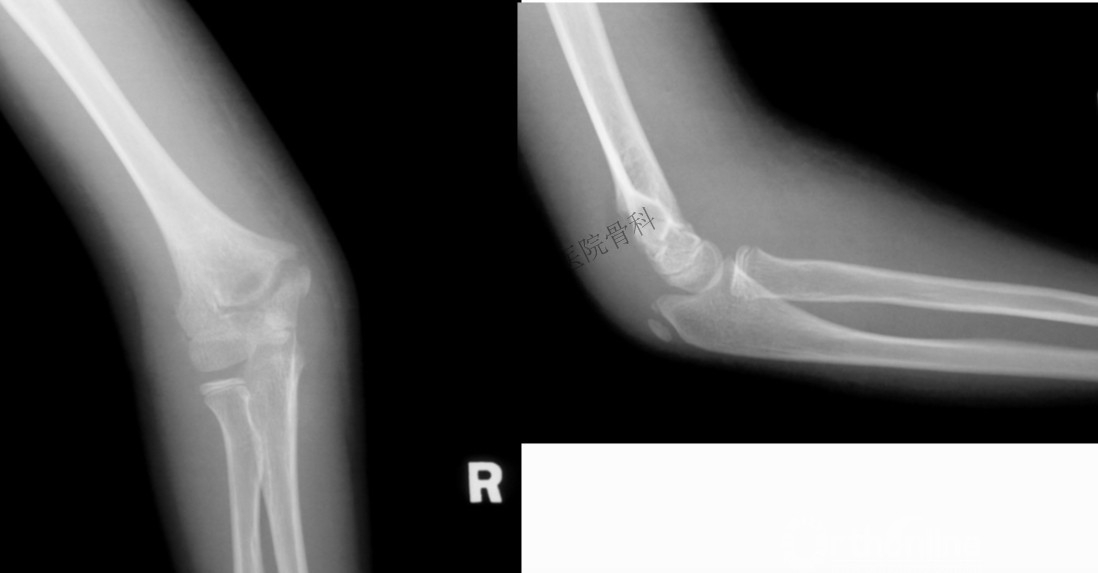

有些隐匿性骨折,仅能从侧位片发现肱骨远端软组织肿胀影,也称八字征。

查体可见肘部肿胀,畸形、压痛和活动受限,x片可见肱骨远端骨折线,有些隐匿性骨折,仅能从侧位片发现肱骨远端软组织肿胀影,也称八字征。有时可同时存在尺桡骨的合并损伤,需加以警惕。